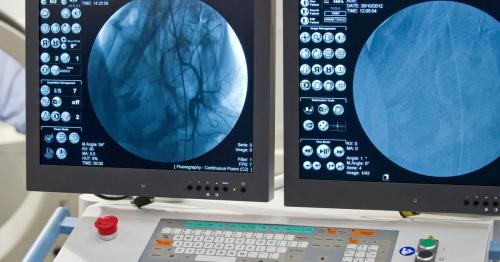

传统X线输卵管造影检查相对来说损伤小,能正确判断输卵管堵塞部位,不过有放射性;超声下造影能动态观察造影剂流动和分布,能得到清晰的图像,无创且没有任何放射性,操作起来简单,诊断价值较高,所以该选择哪种造影检查一目了然。